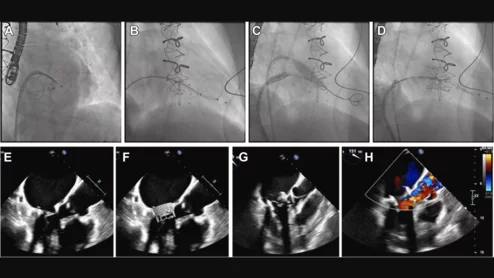

CCTA characterization of a chronic total occlusion with angiographic correlation during percutaneous coronary intervention.

Researchers reviewed dozens of studies to evaluate the long-term value of using CCTA guidance to perform PCI on patients with complete blockages.